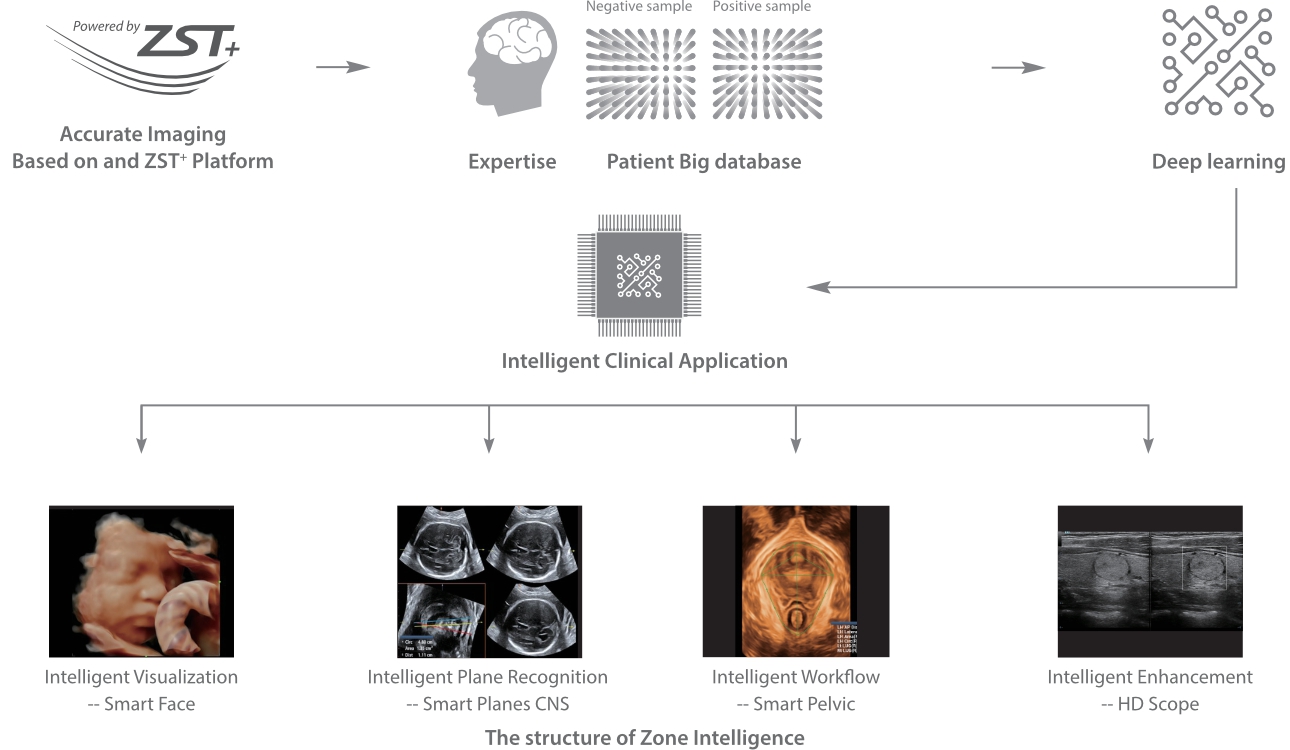

С момента основания компания Mindray непрерывно ищет новые способы повышения точности диагностики. Основанная на самой передовой технологии ZONE Sonography? новая платформа ZST+, выводит качество ультразвуковой визуализации системы Resona 7 на более высокий уровень за счет использования зонного сканирования и канальной обработки данных.

Обеспечивая качество изображения уровня премиум, Resona 7 также повышает клинические возможности исследования при помощи революционной системы V Flow, предназначенной для оценки гемодинамических показателей сосудов; обеспечивает интеллектуальное получение из 3D данных наиболее важных проекций для диагностики ЦНС плода. Сочетая в себе интуитивно понятное сенсорное управление с распознаванием жестов и все важные клинические характеристики, передовая система Resona 7 настоящая новая волна в сфере ультразвуковых инноваций.Благодаря перечисленным выше характеристикам, Resona 7 является доступным решением премиум-класса, которое удовлетворяет высоким требованиям клинической точности и эффективной диагностики в условиях современной перегруженной больничной среды.